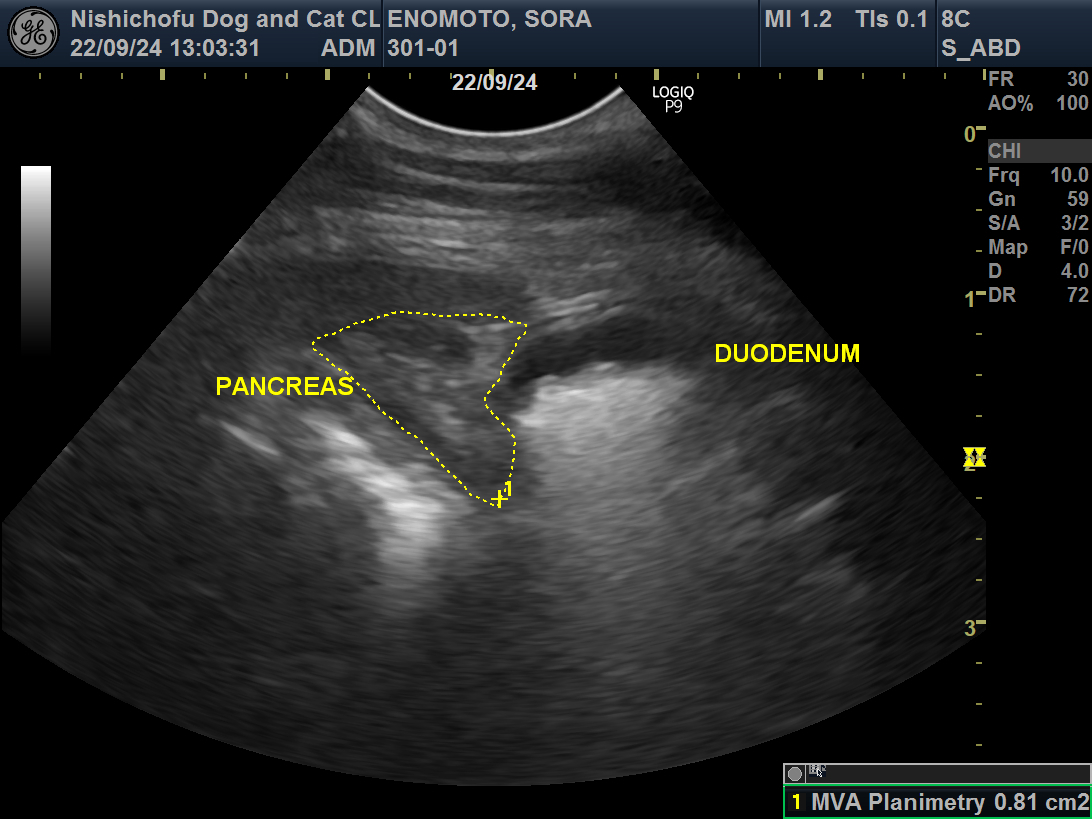

炎症を起こしている膵臓(PANCREAS)。